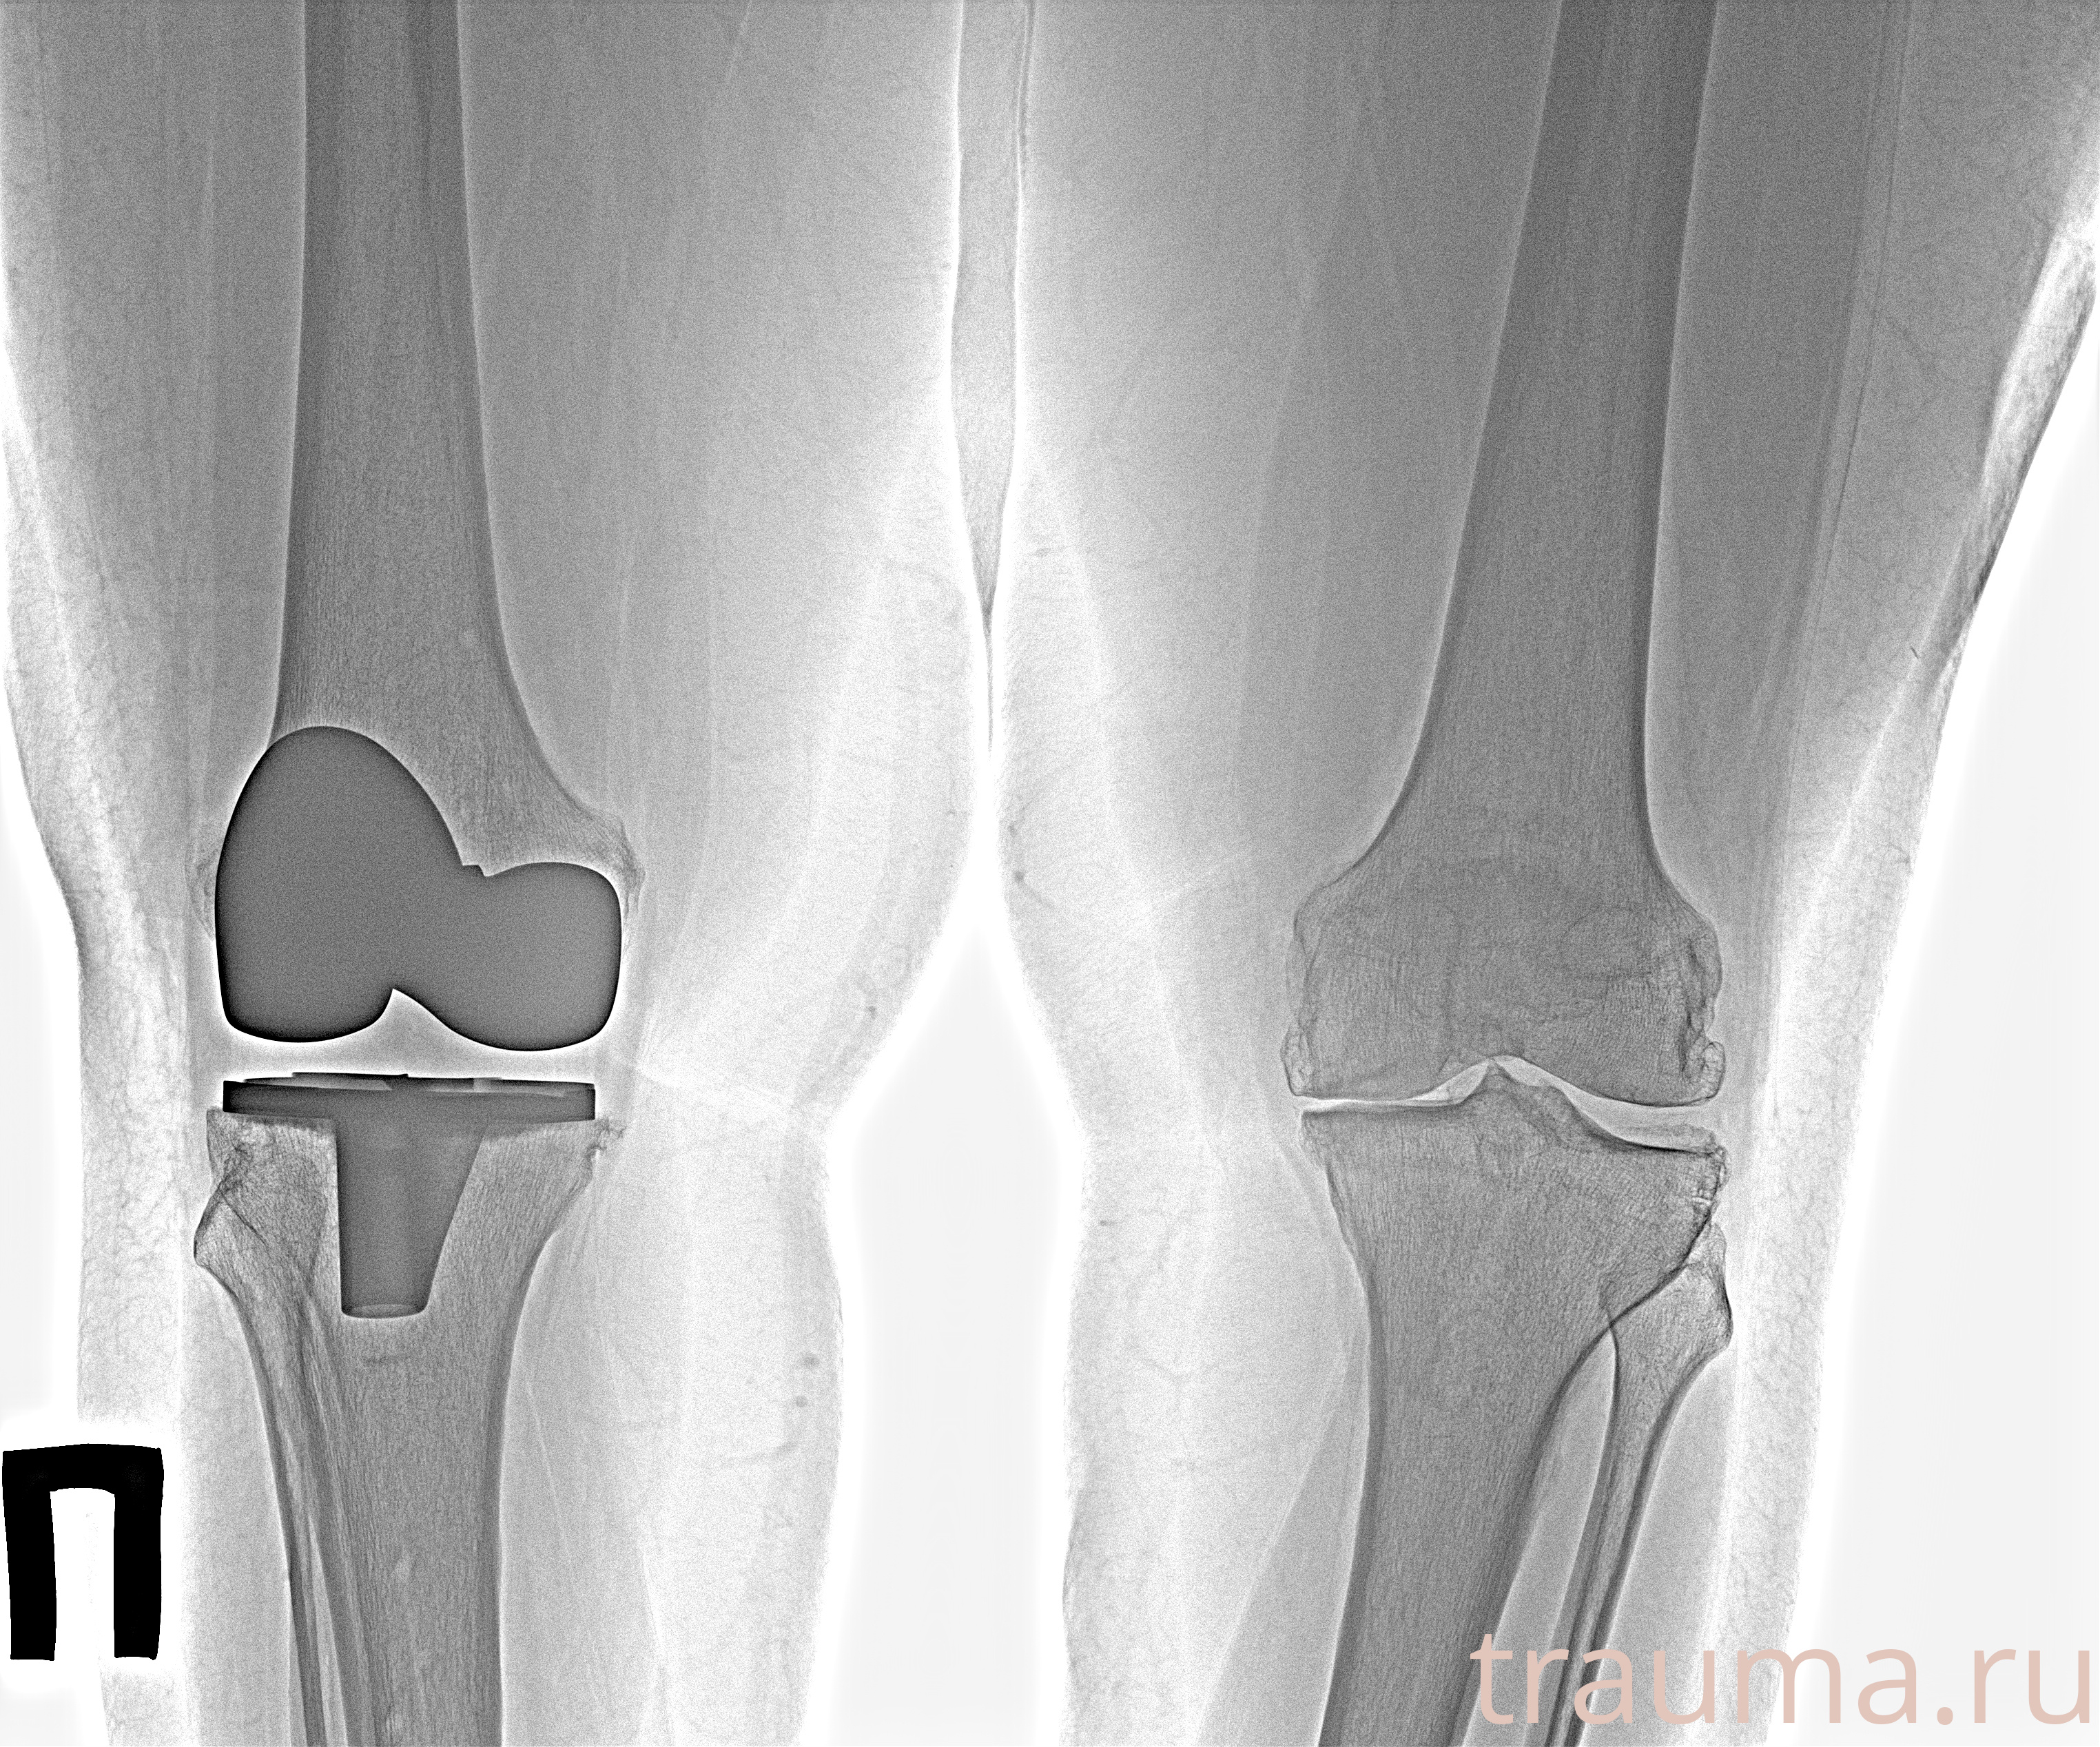

Рентгенограммы

Рентген на дому: по вашему адресу приезжает врач-рентгенолог, травматолог-ортопед с мобильным рентгеновским аппаратом, проводит диагностику травмы или заболевания, делает необходимые рентгенограммы, дает рекомендации по дальнейшему лечению. Получить качественные снимки в домашних условиях возможно благодаря уникальной методике, разработанной МосРентген Центром для института  Склифосовского